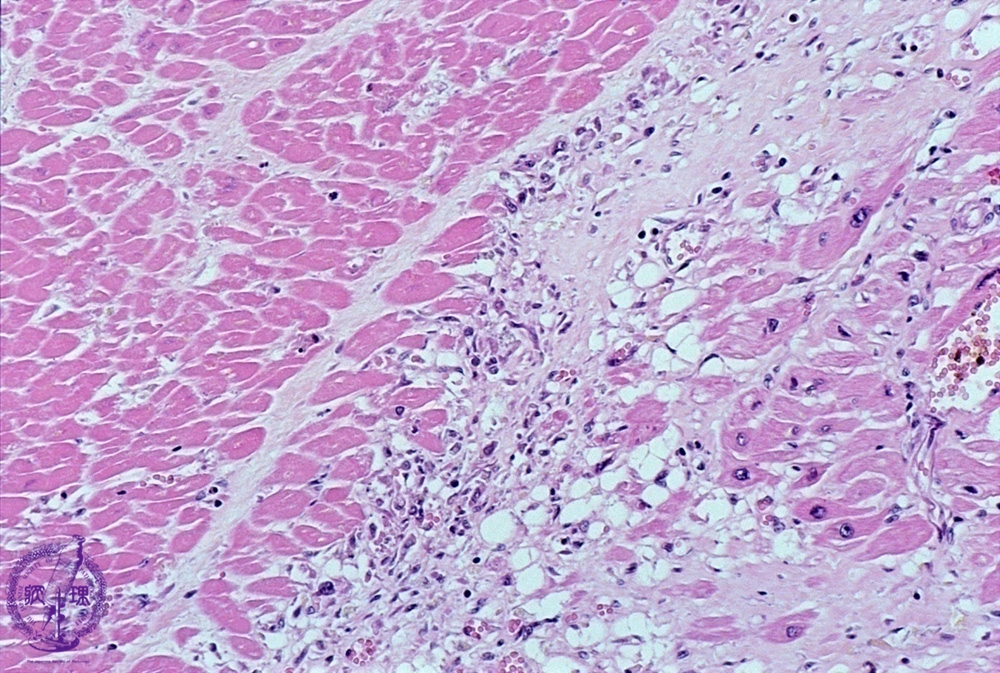

- 3.Cardiovascular system

- ★(2)Myocardial infarction (acute)

Microscopic image (HE, low power): Healing infarct at 3 weeks. The infarcted area comprises necrotic myocytes with karyorrhectic debris, capillary and fibroblastic proliferation and a lymphohistiocytic infiltrate.